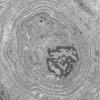

VASCULAR

Hypoxia-Ischemia, fetal-neonatal

White Matter (11)